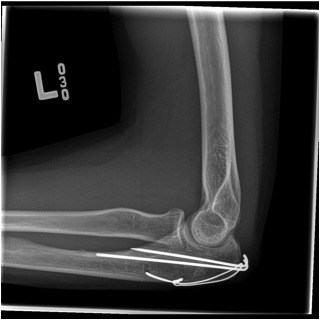

Tension band wire

Indication

Fracture proximal to center of rotation / midpoint of trochlea

Convert tensile distraction force of triceps into a compressive force

Technique

- fix with unicortical K wires

- drill hole in ulna distally

- pass 20 gauge wire and form figure of 8 wire about wires, can pass under triceps

- twist via 2 knots